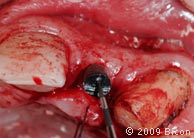

12. Расщепление костной ткани с помощью расширяющего долота 5,5 мм в области верхнего левого бокового резца.